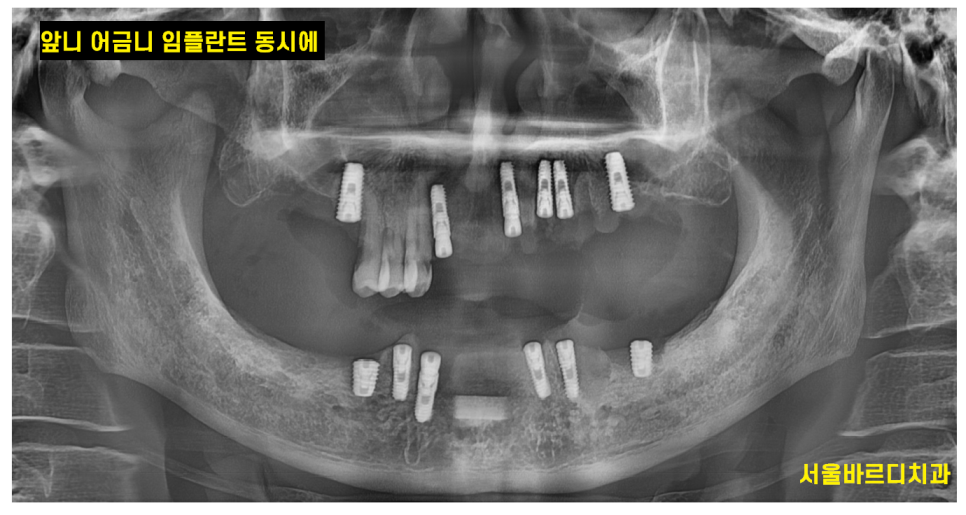

앞니 어금니 임플란트 동시에 수술합니다.

240513

위,아래 임플란트를

앞니 어금니 임플란트 동시에 수술했습니다.

하루에 치료해드렸는데요~

이렇게 되면 수술에 대한 부담감도 덜어드릴 수 있고

치료기간도 현저하게 줄어들죠~

보철을 제작할 때에도

앞니와 어금니 동시에 붙여드릴 수 있는데요~